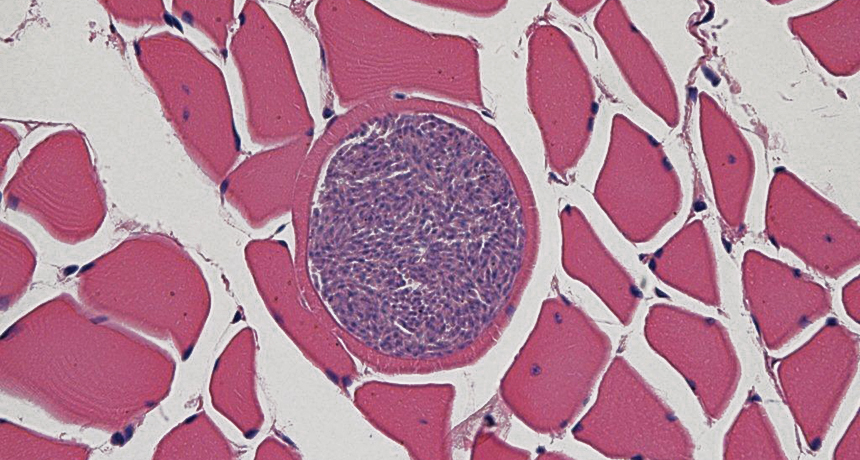

NEW NEIGHBORS As the Arctic emerges from a deep freeze, parasites including Sarcocystis pinnipedi (shown, purple) are able to infect animals that they have never encountered before.

Grigg and his colleagues found that the parasite, a microscopic creature shaped like a crescent moon, also infects about 80 percent of ringed seals (Pusa hispida) but doesn’t make them sick. The parasite, which Grigg and his colleagues dubbed Sarcocystis pinnipedi, invades cells and can cause inflammation that damages tissues. In ringed seals, the parasite gets into cells, but the animals protect themselves from inflammation by walling the microbes off in cysts.